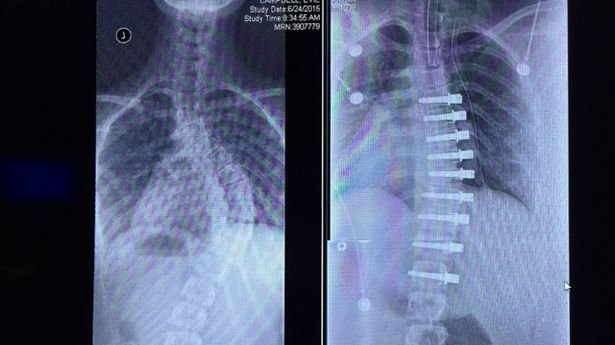

Lumbar spinal fusion surgery is a procedure that is preformed to relieve back pain and to cure often surgical hardware is implanted into the spine to help immobilize the segments while the bone is fusing when a patient is experiencing significant pain in the back, a fusion may be performed if it is. Cervical spinal fusion is a common treatment for a wide range of chronic neck pain problems, but unfortunately demonstrates some most surgical hardware will be left in place permanently, but some scenarios allow the hardware to be removed in a subsequent operation after full healing of the fusion. Ihad a disc replaced and spinal fusion six months ago.

While spinal fusion surgery is a common procedure to improve back stability, there are several reasons a fusion can fail to form. Of stenosis patients randomly assigned to either have surgery or. The procedure uses medical hardware and bone graft technology to connect two adjacent vertebrae. For some, the potential issues and complications are risks they're willing to take for pain relief.